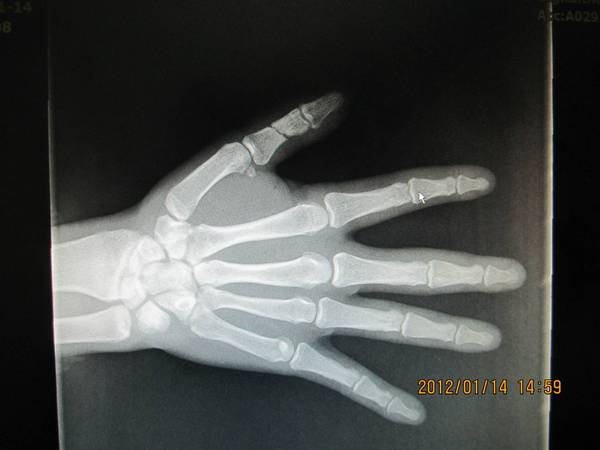

RE: 拇指近节缺损性离斷--邻指指动脉岛状皮瓣桥接再植术后50

术后50天复查,拔出克氏针,知道患者继续进行功能锻炼。